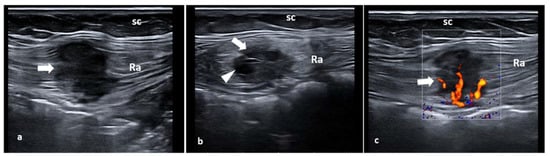

6. Inguinal Canal Endometriosis